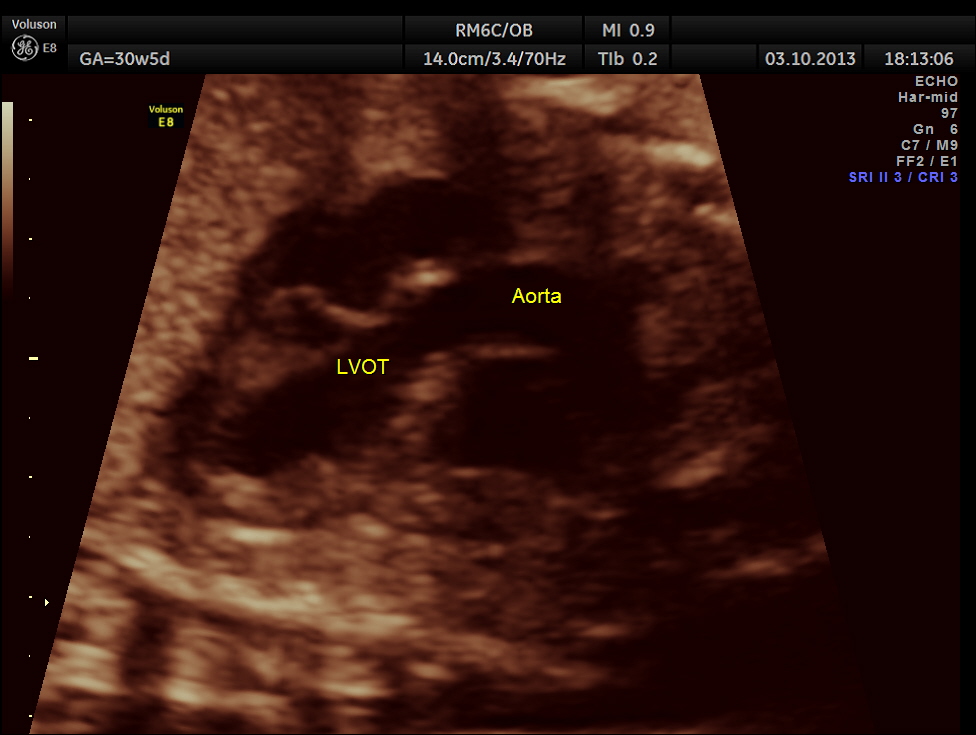

The following pictures belong to two scans done at 31 weeks of gestation.

The rest of the scan appeared normal.